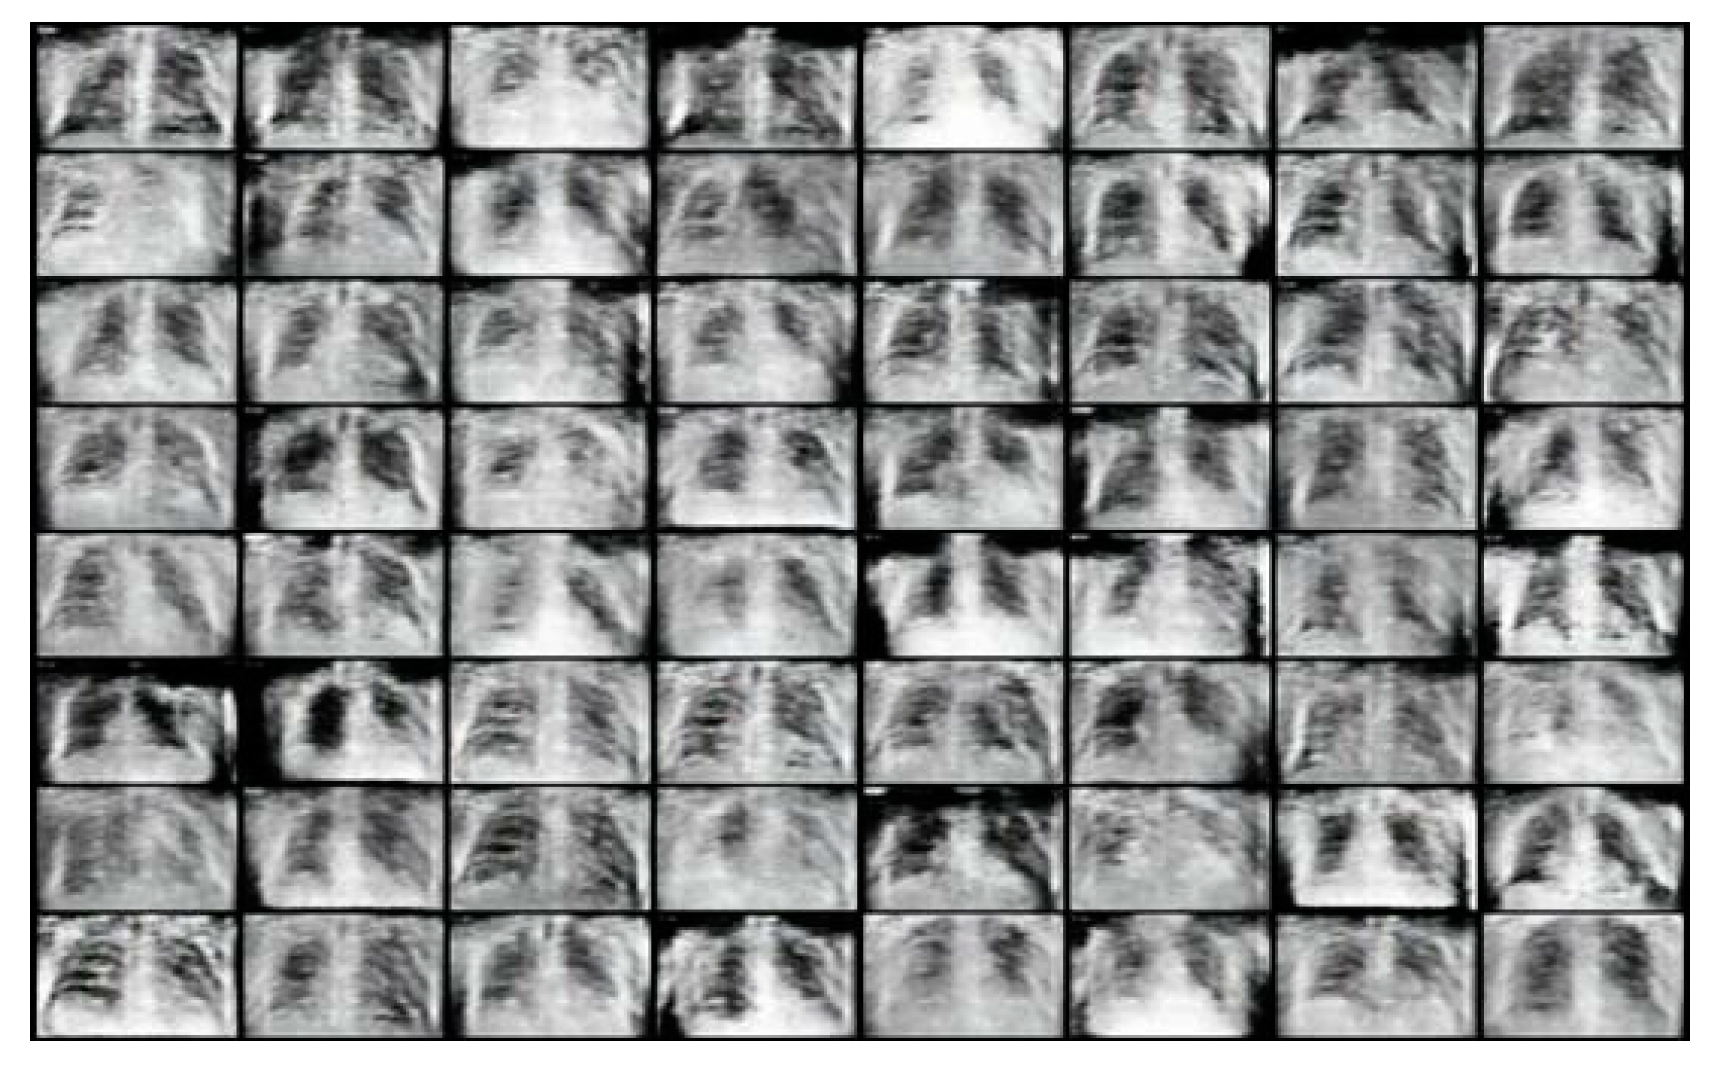

We can see in Figure 2 below, that at 50 epochs, the DCGAN model is able to generate images that resemble chest X-ray images, although the images are very pixelated and blurry.

Figure 2.

Generated COVID-19 positive chest X-ray images with dataset of 1000 images at 50 epochs.

In Figure 3 below, we observed that the images at 500 epochs produced by the DCGAN are now less blurry as compared with the images in Figure 2 and have a much higher resemblance to the COVID-19 chest X-ray images used to train the DCGAN model. Thus, showing that the DCGAN model improves and generates higher-quality images as training progresses.

Figure 3.

Generated COVID-19 positive chest X-ray images with dataset of 1000 images at 500 epochs.